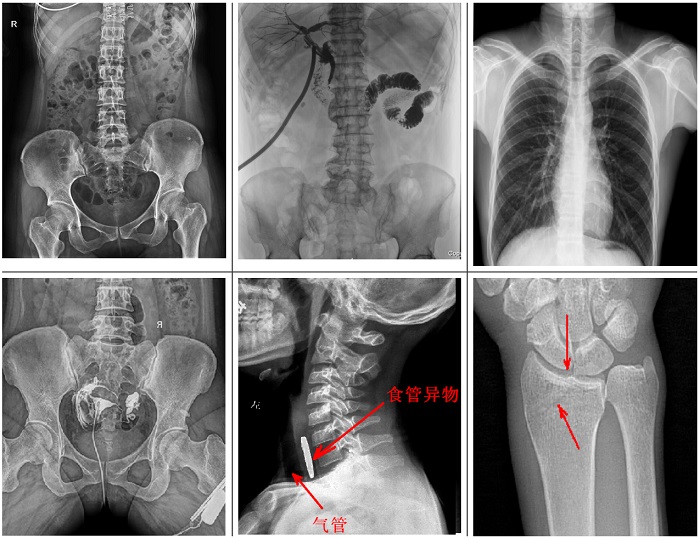

不同于傳統(tǒng)靜態(tài)懸吊DR,普利德多功能懸吊動(dòng)態(tài)DR搭載動(dòng)態(tài)平板探測(cè)器,同時(shí)具備數(shù)字?jǐn)z影、透視、造影功能,全脊柱、全下肢圖像拼接等功能,臨床應(yīng)用更加廣泛,可通過(guò)動(dòng)態(tài)實(shí)時(shí)連續(xù)成像,對(duì)于重疊部位病灶或者易被遮擋的病灶進(jìn)行多角度動(dòng)態(tài)觀察,極大的提升篩查診斷的精準(zhǔn)性。

可供各級(jí)醫(yī)院進(jìn)行人體頭部、頸部、胸部、腹部、腰椎、四肢等部位的臥位、正位、側(cè)位、斜位的數(shù)字化攝影、透視及造影檢查;適用于各級(jí)醫(yī)院臨床各個(gè)科室,滿足放射科、體檢中心、影像中心、內(nèi)科、外科 、急診科、骨科、創(chuàng)傷科、消化科等科室的多種臨床檢查需求。